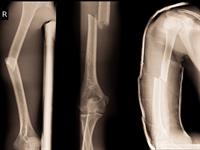

Kaulu lūzums ir daļējs vai pilnīgs kaula viengabalainības zudums. Kaulu lūzumus iedala:

- slēgtos lūzumos (netiek skarti apkārtējie audi un āda) un

- vaļējos lūzumos (ir bojāti apkārtējie audi un āda un no brūces var redzēt kaulu gabalus).

Kaulu lūzumi

Slēgts un vaļējs lūzums

Svarīgi!

Lai diagnosticētu kaulu lūzumu, jāveic rentgens.